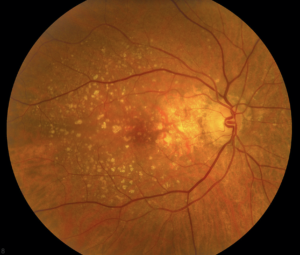

Este tipo de degeneración es bastante común. Aproximadamente el 80% (8 de cada 10) de las personas con DMRE tienen el tipo de degeneración seca. La DMRE seca se produce cuando algunas partes de la mácula se vuelven más delgadas con la edad, causando una aglomeración de proteínas llamada drusas. Esto hace que pierda visión central lentamente. Aún no hay tratamiento para la DMRE seca.

Cuando tiene DMRE, pudieran aparecer zonas oscuras en su visión central.